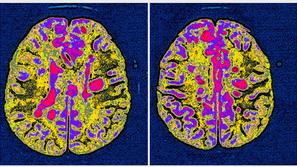

Neozdravljiva Multipla skleroza: Bolniki, ki morajo biti pravi umetniki Avtoimuna bolezen, ki povzroča vnetje v osrednjem živčevju.